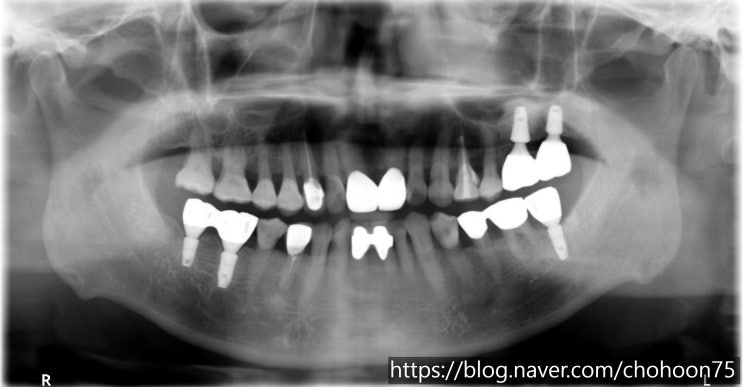

[조훈치과] 과도한 치아 마모, 교모로 수직 고경이 감소된 환자분의 보철치료 및 임플란트 치료 증례

안녕하세요. 조훈 치과입니다. 치아를 사용함에 따라 점진적으로 치아가 닳고 마모가 되는 것은 자연스러운...